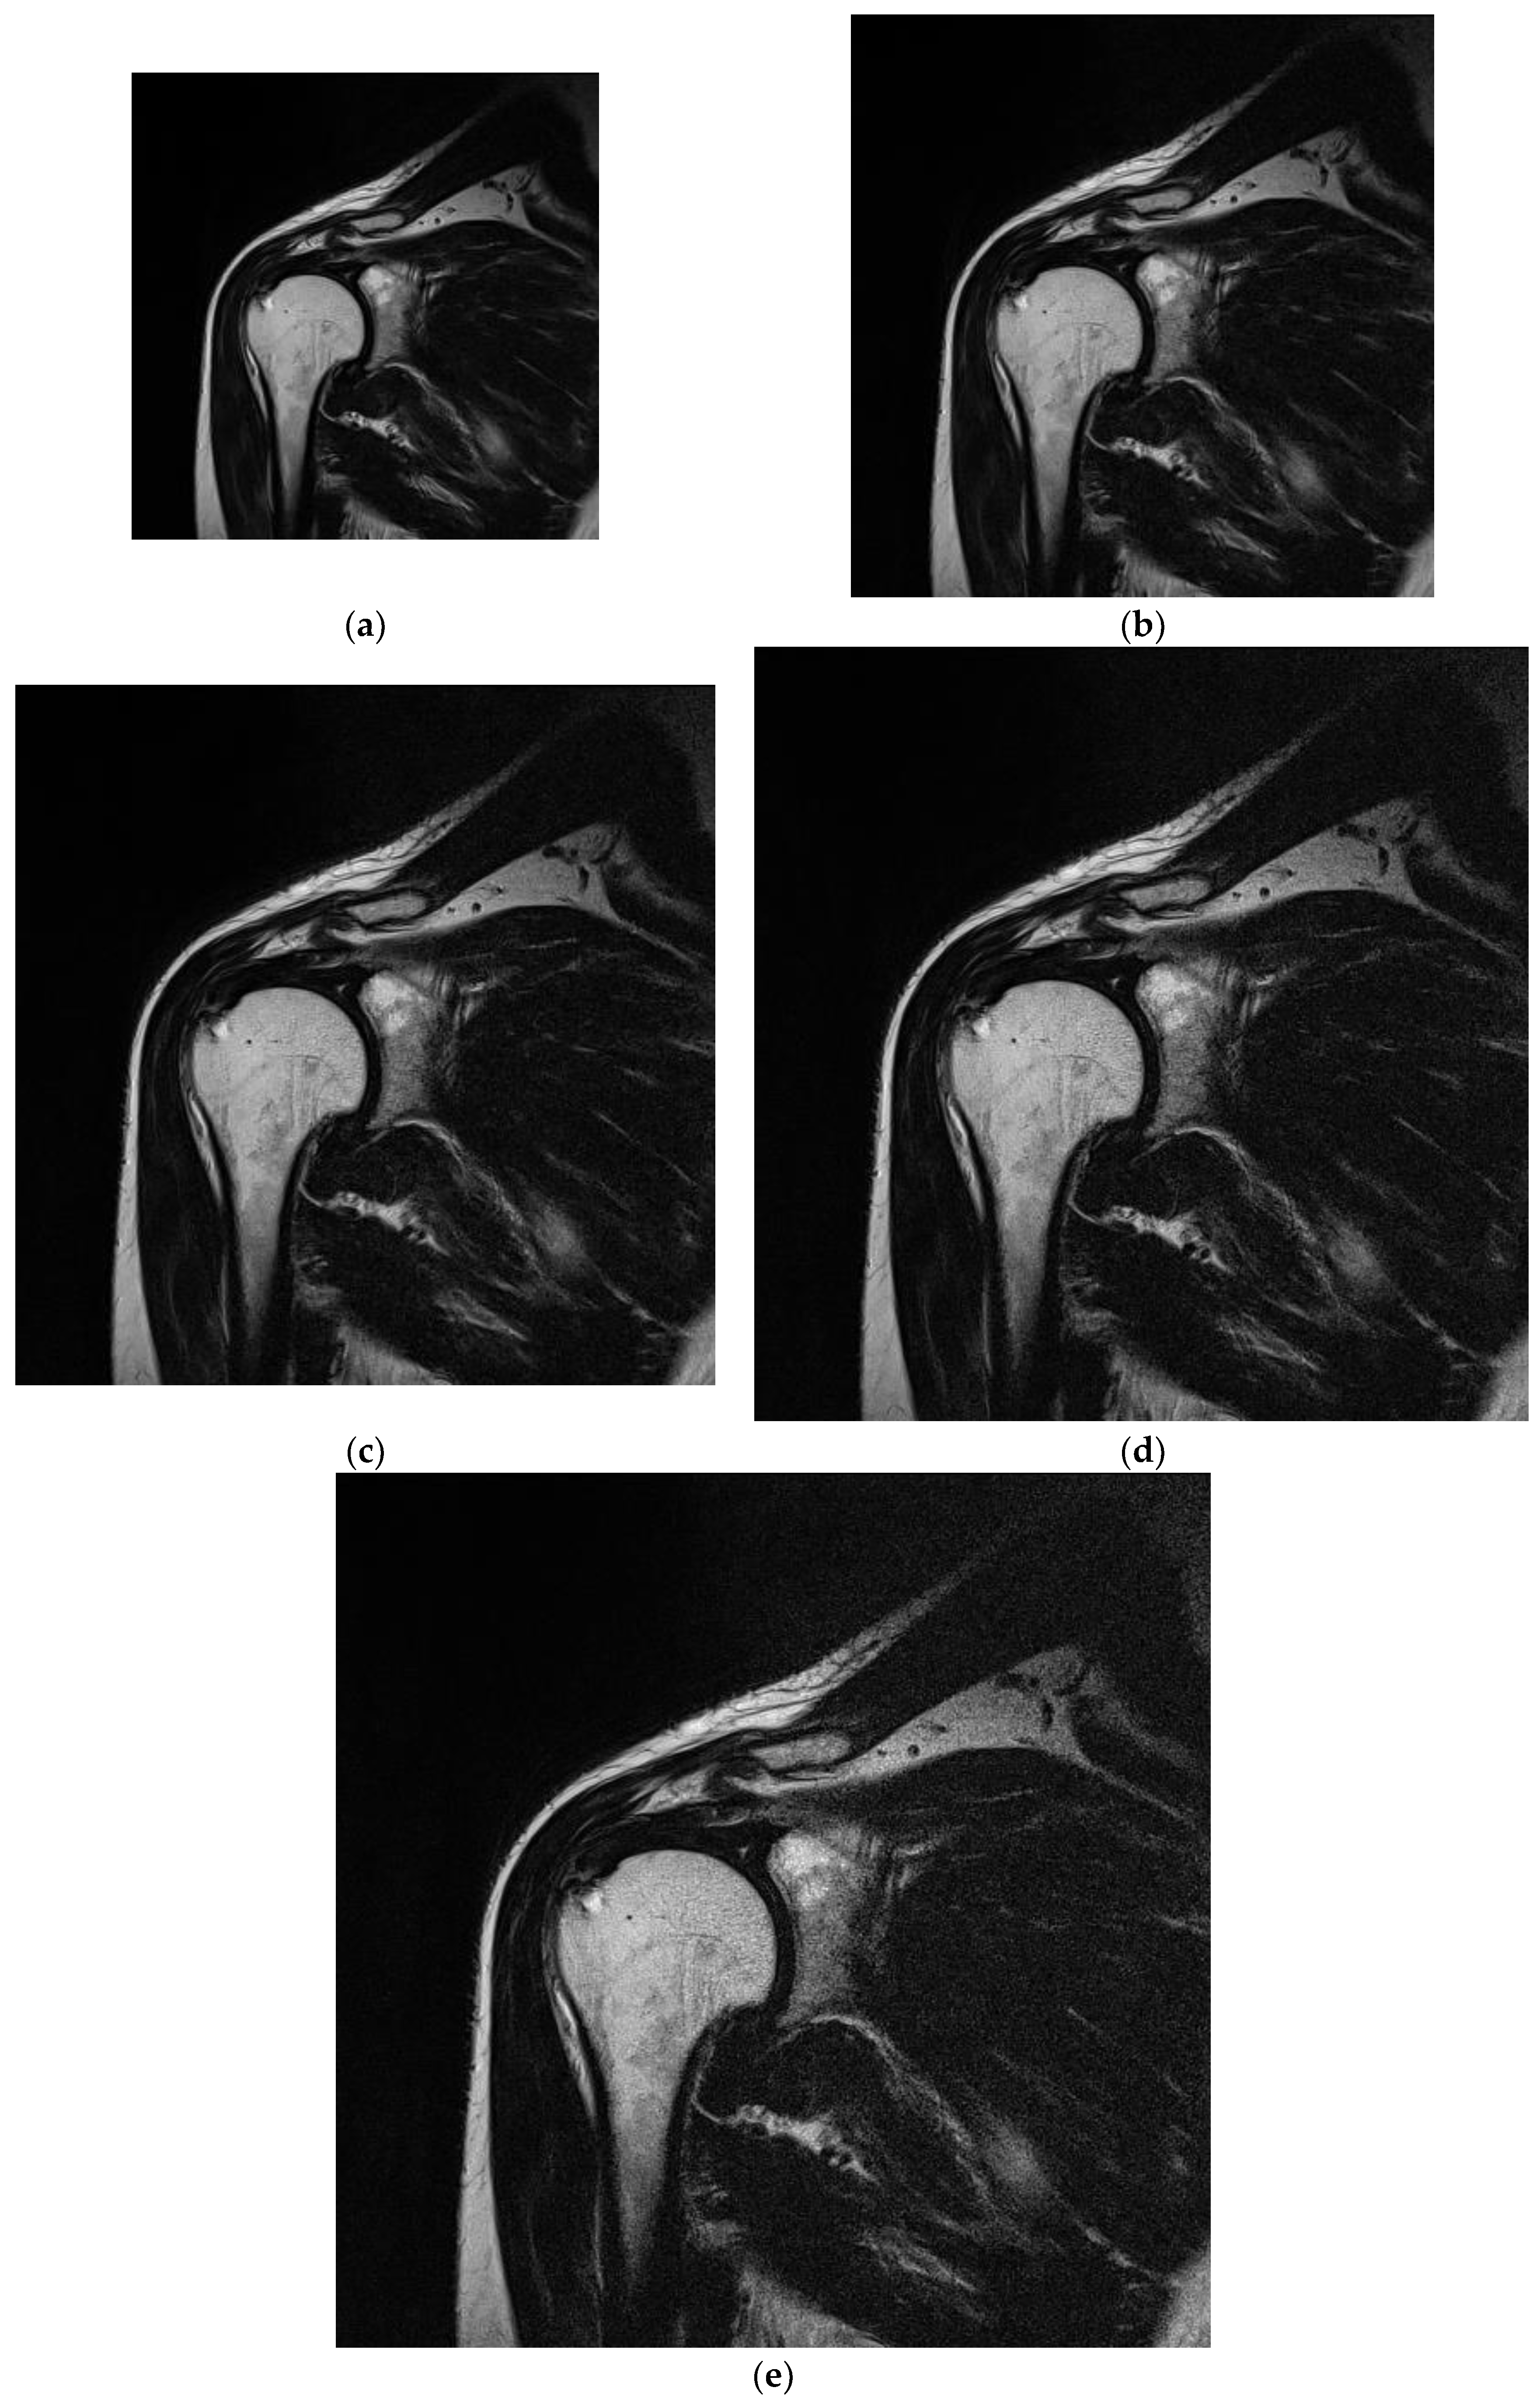

The study protocol was designed based on guidelines of the Declaration of Helsinki and the Good Clinical Practice Declaration Statement. All images were anonymized before processing to ensure personal data safety. Furthermore, written acceptance was obtained from the Local Ethics Committee to conduct this study (No. 155/KBL/OIL/2017 dated: 22 September, 2017). Data from 20 patients (12 women and 8 men) between the ages of 34 and 61 years were used in the study. T2-weighted coronal images of shoulders were obtained during normal diagnostic procedures with added sequences with changed matrix size. The exclusion criteria included patients with implants or other foreign bodies that produced susceptibility artifacts; furthermore, movement during the examination was considered a negative selection criterion because it caused image artifacts that affect the image analysis. To provide stable conditions for the image creation, patients with BMI in the range of 20–26 were included in the study. The T2-weighted coronal sequences of the shoulder were analyzed (Figure 4). For this study, we selected images of tissues that were free of pathologies. Images were selected to satisfy stable (repetitive) conditions for texture feature analysis.

Figure 4.

Sample analyzed images acquired for matrices with various sizes under the same FOV. (a) 256 × 256; (b) 320 × 320; (c) 384 × 384; (d) 448 × 448; (e) 512 × 512.